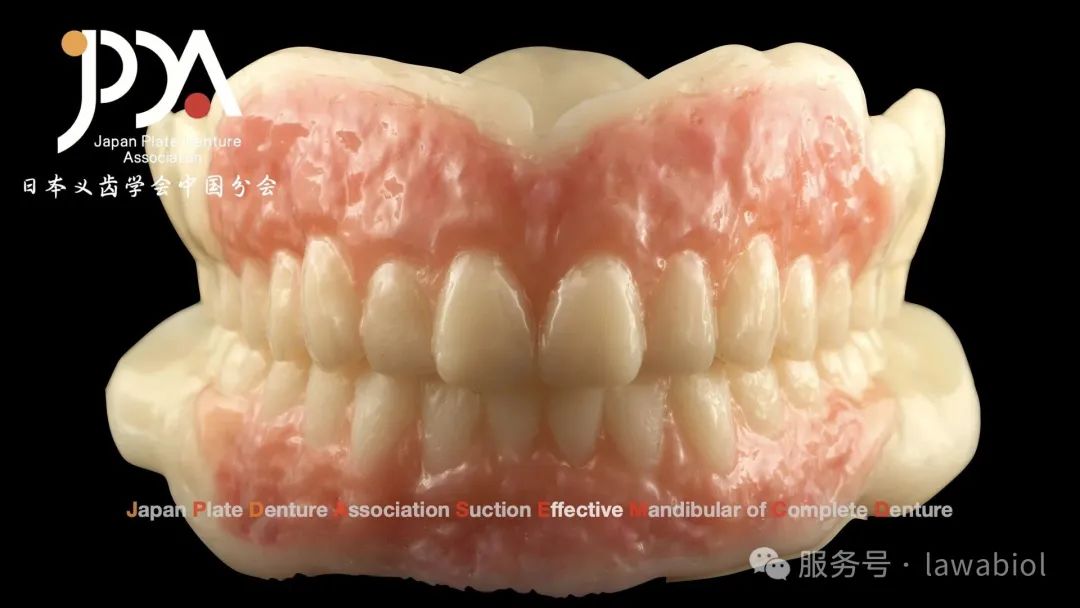

杭州拉瓦与爱迪特共同推出的"数字化全口整体解决方案"成为会议焦点。现场通过数字化3D打印技术,演示了"一体式"与"分体式"过渡义齿的制作过程,精准适配复杂牙槽嵴形态。

佐藤勝史先生为日本患者试戴过渡义齿后,拉瓦基于试戴数据,使用数字化切削设备实时完成终义齿制作,完整呈现了数字化"即刻修复"的全流程。拉瓦展台展出的数字化解决方案以其精准度和高效性,吸引了众多参会者交流探讨。